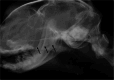

Feline nasopharyngeal stenosis (NPS), characterized by narrowing of the nasopharyngeal passage, results in chronic stertor and increased inspiratory effort. While rhinoscopy is the definitive diagnostic modality for NPS, the utility of nasopharyngeal radiography in diagnosis remains under-documented. The purpose of this study is to evaluate the diagnostic accuracy and describe the characteristic radiographic findings in cats with NPS by comparing radiographic findings in cats with stertor but without stenosis. This is a multicenter, retrospective, cross-sectional study. Fifty-two cats with stertor who underwent both rhinoscopy and lateral nasopharyngeal radiography were included. They were divided into two groups: those with NPS (n = 21) and those with stertor without stenosis (ND group, n = 31). Radiographs were reviewed by two board-certified radiologists to determine the presence, location, and morphology (broad or membranous) of NPS, as well as the morphology of the soft palate and the presence of oropharyngeal gas. Radiographic evaluation demonstrated a high diagnostic accuracy for NPS with a sensitivity of 100%, specificity of 83.9%, and overall accuracy of 90.4%. The radiographic morphology of the NPS was broad in 18 cats and membranous in 3 cats. A "bent" soft palate was observed only in the NPS group (19%, n = 4). The presence of oropharyngeal gas was similar in both groups (57.1 vs. 58.1%). However, because radiographic diagnoses were made by consensus between two radiologists, the reported accuracy may be overestimated. Given its high sensitivity, nasopharyngeal radiography serves as an effective initial screening tool for NPS, likely streamlining the diagnostic pathway in cats with stertor.